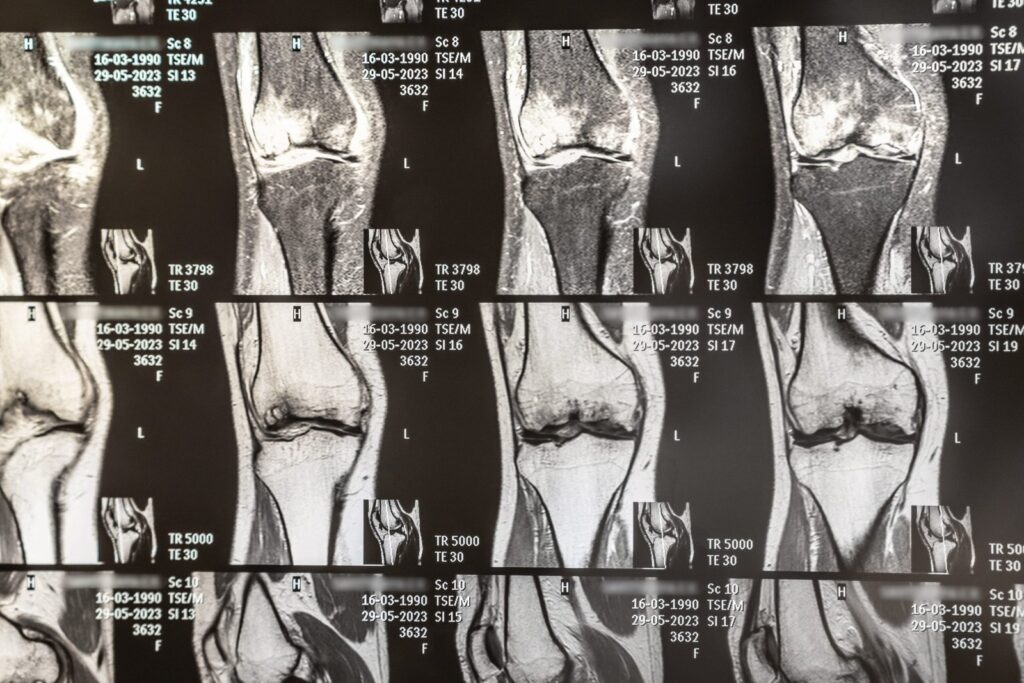

- Ressonância magnética (RM): produz imagens detalhadas dos tecidos moles, como músculos, ligamentos e tendões, sendo ideal para avaliar lesões musculares, rupturas ligamentares e condições crônicas, como osteoartrite.

Exames como a ressonância magnética e a tomografia computadorizada podem detectar padrões de sobrecarga em articulações e músculos que ainda não se manifestaram como lesões. Isso permite que o atleta ajuste seu treino para evitar danos futuros e mantenha a intensidade ideal sem comprometer sua saúde.

Lesões por uso excessivo, como as fraturas por estresse, são comuns em esportes de alto impacto. Exames de imagem, como a tomografia, podem identificar microfraturas e áreas de maior desgaste ósseo. Com esses dados em mãos, o atleta pode adaptar seu treinamento e evitar uma lesão mais séria.